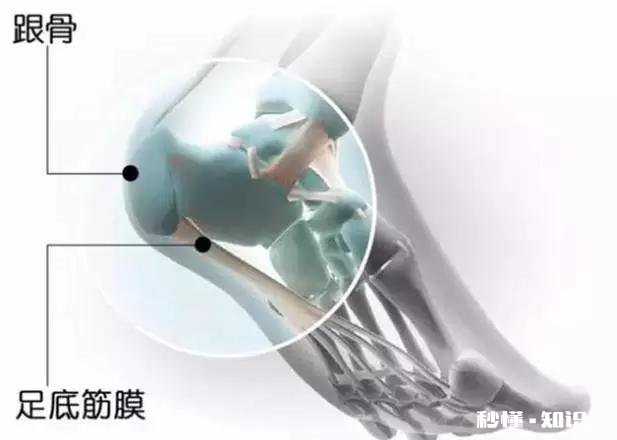

足底筋膜,在我们的脚底,从跟骨往前延伸到脚趾下,把我们的脚趾都往上翘,能摸到脚底变硬了,那就是我们的足底筋膜 。当我们的脚趾往上翘的时候,附着在跟骨下方的肌腱是被往前拉的,时间久了,骨刺就被拉出来了!这才是足底骨刺的最大原因!

足底筋膜从后跟往前延伸到脚趾下方 。

跟骨的骨刺大多数都不是垂直向下的,而是往前的 。所以骨刺怎么会扎到肉里呢?